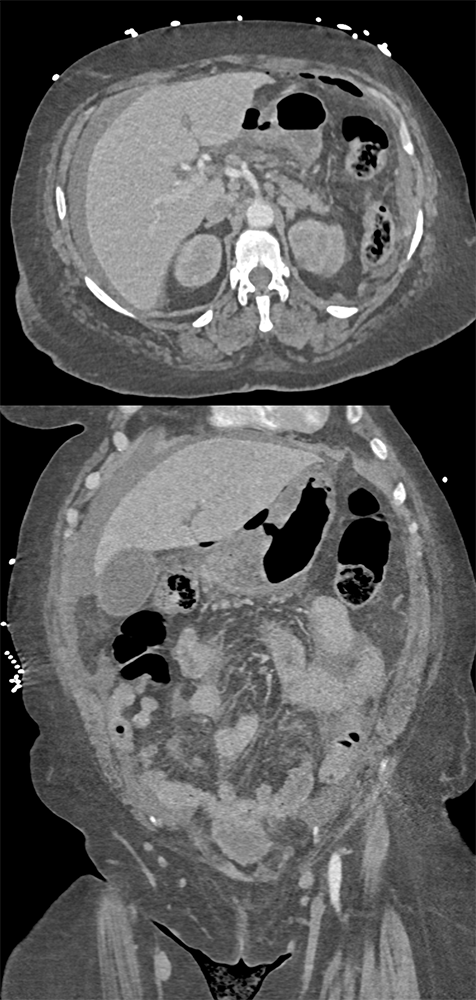

Perforated Benign Gastric Ulcer ![]() |